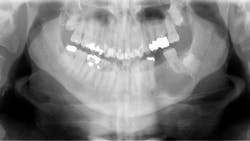

Patient: 66-year-old male

- Large radiolucency in the left mid-body of the mandible

- No oral lesions or vestibular swelling

- No extraoral visual or palpable swelling in the area

- No cervical lymphadenopathy